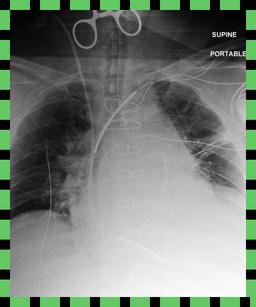

We found that many lateral acquisitions in the dataset were unexpectedly labelled as frontal (Figure 7(a)). Some images contained only noise (Figure 7(b)), non-human samples (Figures 7(d) and 7(e)) or incorrect anatomy (Figure 7(g)). Often, acquisitions with an incomplete field of view (FOV) (i.e., the lungs are not completely visible) were repeated (Figure 7(c)). Lastly, post-processed images were detected by the algorithm such as contrast-enhanced scans (Figure 7(i)) that are not often used for diagnostic purposes in clinical practice.

Curation of imaging datasets

CXR datasets [36] often contain multiple image acquisitions in a single visit due to data quality issues such as a limited field-of-view or scanning the wrong body part (Figure A.7). Unlike [9, 32, 81], we conduct curation to choose higher quality images among the potential candidates instead of performing a random selection. For this step, a separate BioViL-T is trained on ‘clean’ studies with single acquisitions and later used in a zero-shot setting to detect out-of-distribution samples [26, 27] arising from the re-imaging process. The candidate is selected as follows: for a margin . This approach is applied to enhance the quality of the temporal classification dataset given its limited size.